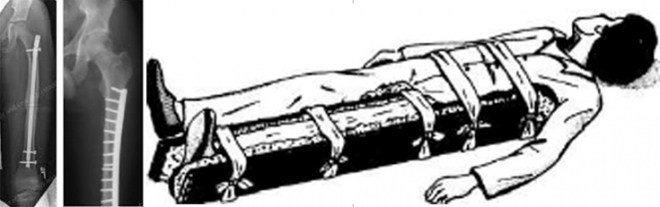

Το κάταγμα του μηριαίου χρειάζεται νοσοκομειακή αντιμετώπιση. Για την μεταφορά ακινητοποιούμε τον μηρό χρησιμοποιώντας νάρθηκα εμπρός και πίσω από το μηρό, εγκλείοντας και το γόνατο.

Το κάταγμα της διάφυσης του μηριαίου αντιμετωπίζεται συντηρητικά μόνο στα παιδιά (μέχρι την εφηβεία) γιατί η χειρουργική αντιμετώπιση μπορεί να προκαλέσει επιμήκυνση του τραυματισμένου σκέλους.

Στους ενήλικες το κάταγμα της διάφυσης του μηριαίου αντιμετωπίζεται χειρουργικά, με ενδομυελικό ήλο στην πλειονότητα των περιπτώσεων. Ο ήλος αυτός ονομάζετο παλαιότερα ήλος Kuntschner, από έναν γερμανό ορθοπαιδικό που τον ανεκάλυψε την δεκαετία του Β΄ Παγκοσμίου Πολέμου. Τον τοποθετούσαν στους γερμανούς στρατιώτες που τραυματίζονταν στις μάχες και σε 1 ½ μήνα τους ξαναέστελναν να πολεμήσουν.

Σήμερα οι ήλοι αυτοί έχουν εξελιχθεί και σταθεροποιούνται περιφερικά και κεντρικά με βίδες που δίδουν πρόσθετη σταθεροποίηση και πραγματικά ο τραυματισμένος μέσα σε 1 ½ μήνα είναι καλά και ικανός να βαδίζει χωρίς πατερίτσες. Η εγχείρηση δε γίνεται μέσω μίας μικρής τομής, με ακτινολογική παρακολούθηση.

Σπάνια και για ειδικούς λόγους το κάταγμα αυτό αντιμετωπίζεται με ισχυρή πλάκα και βίδες.